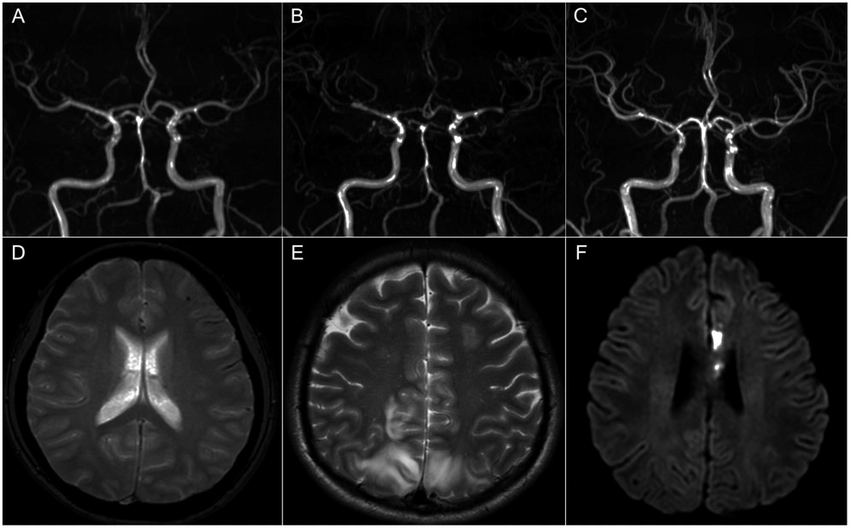

Chẩn đoán RCVS dựa trên tiền sử bệnh, các triệu chứng, khám sức khỏe toàn diện và kết quả chụp ảnh mạch máu não. Chẩn đoán hình ảnh thường gồm chụp mạch, chụp MRA hoặc CTA có thể cho thấy co thắt trong các mạch máu bị thu hẹp.